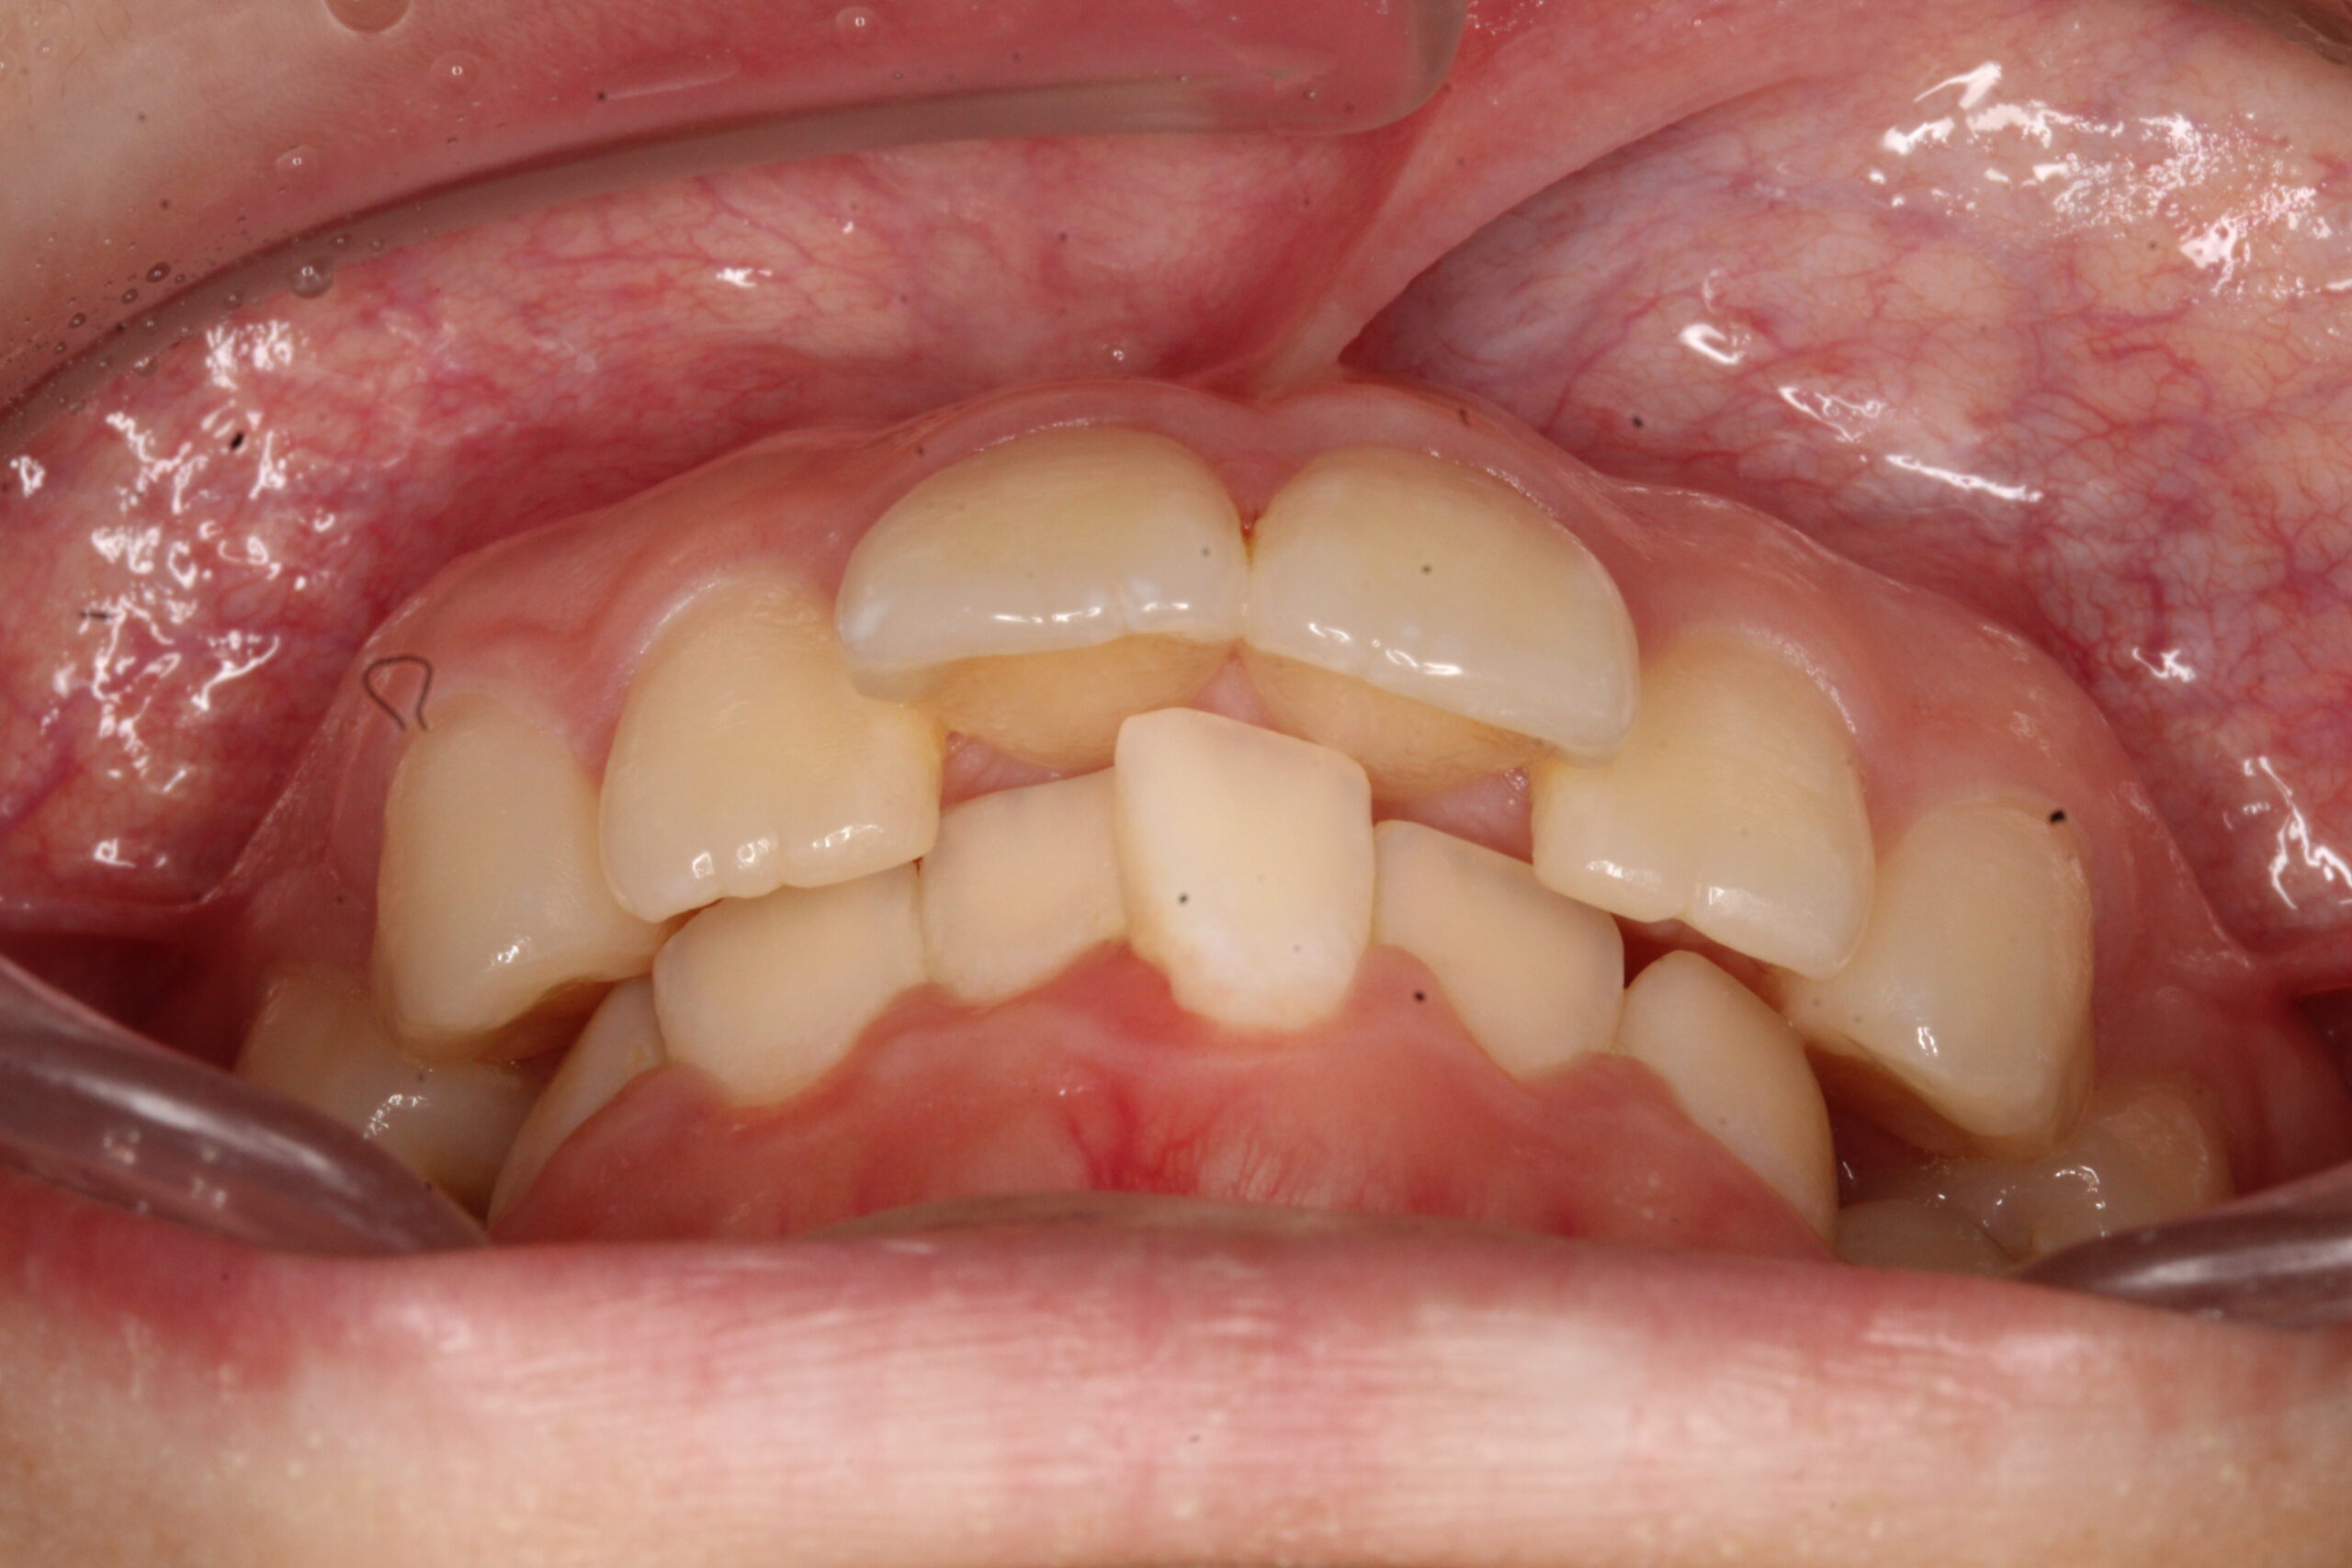

矯正術前:前歯部あおり

矯正術後:前歯部あおり